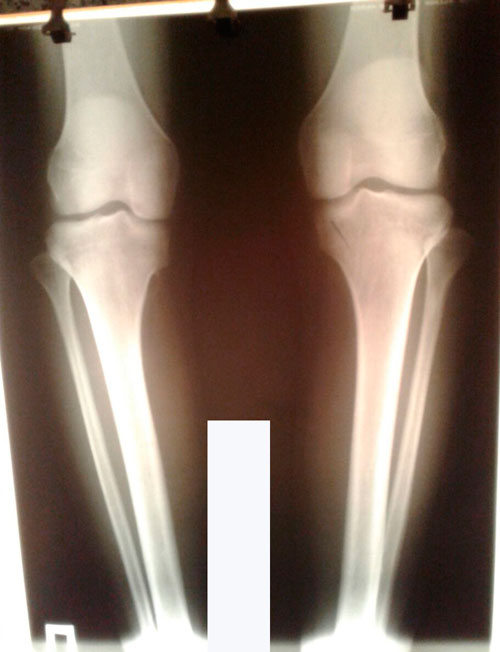

Исходник - 19 лет.

Дата операции 25.05.2017г.

Дата снятия аппаратов 10.08.2017г.

Срок лечения 75 дней.